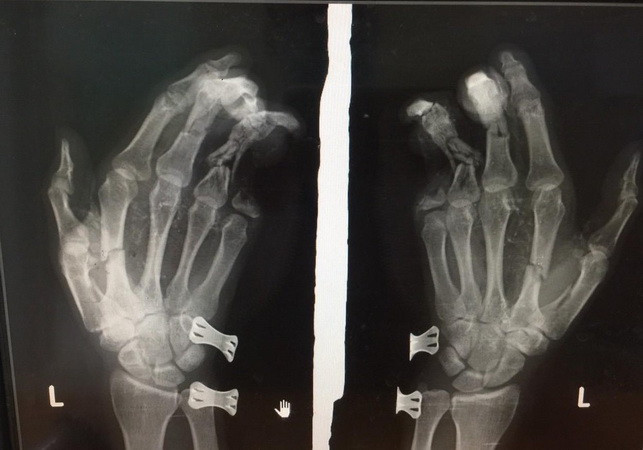

Điện thoại phát nổ khi đang sạc, nam thanh niên bị dập nát bàn tay ảnh 1Phim chụp bàn tay của nam thanh niên bị tổn thương do điện thoại phát nổ.

Hậu quả, bàn tay trái của anh Duy dập nát, tổn thương nặng và ngón út bị cụt mất 2 đốt. Tại Bệnh viện Đa khoa II Lâm Đồng anh Duy  được sơ cứu, chụp phim và đưa vào phòng phẫu thuật khâu lại viết thương.

Theo lãnh đạo Bệnh viện Đa khoa II Lâm Đồng, ngón út của nạn nhân bị mất hai đốt không thể phẫu thuật ghép nối. Đây là bài học cảnh tỉnh cho những người vừa sử dụng điện thoại vừa sạc pin./.